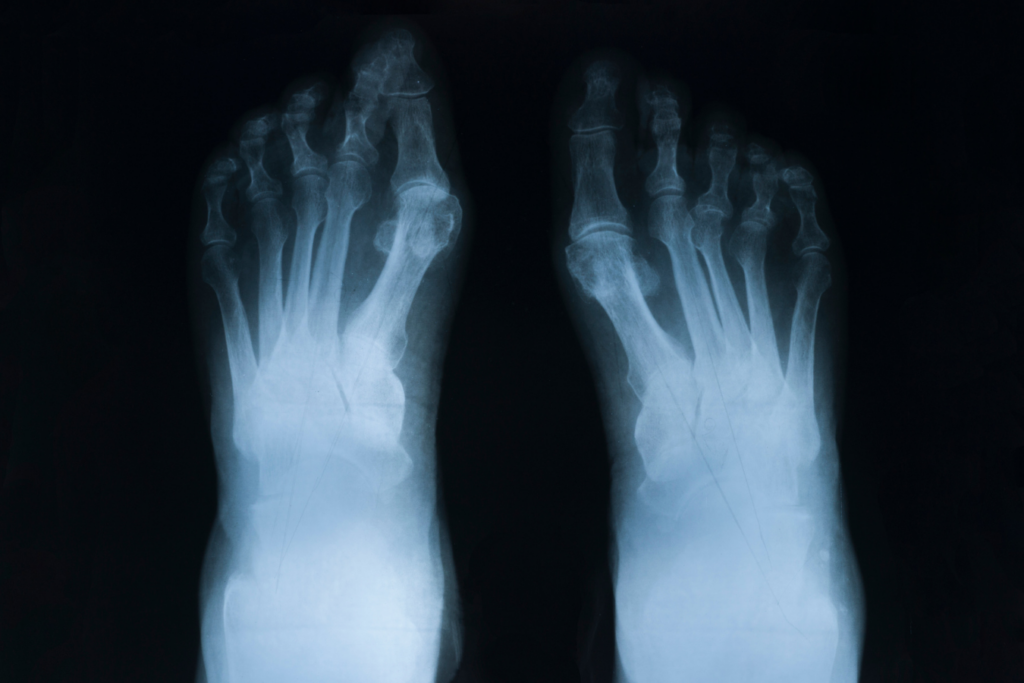

Effects of rheumatoid arthritis on the body

Effects of rheumatoid arthritis on the body What Is Inflammatory Arthritis Uk Rheumatology is an area of medicine that specialises in the diagnosis and management of conditions which can. Inflammatory arthritis is a chronic disease in which your immune system misidentifies your own body tissues as harmful germs or. Inflammation is normally an important tool in the immune system. Inflammatory arthritis is a collective term for a group of conditions, including rheumatoid. What Is Inflammatory Arthritis Uk.